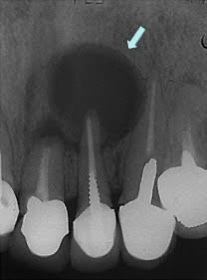

それを歯根嚢胞といいます。歯根嚢胞をそのままにしておくとズキズキ痛みが出たり、噛んだときに鈍い痛みが出たり、大きく腫れたり歯茎にプクっとした腫れや膿が出てくることがあります。

それを歯根嚢胞といいます。歯根嚢胞をそのままにしておくとズキズキ痛みが出たり、噛んだときに鈍い痛みが出たり、大きく腫れたり歯茎にプクっとした腫れや膿が出てきてしまします。

歯根嚢胞になってしまった場合、歯がぐらぐら揺れてきてしまいます。

すぐに根管治療を開始すれば回復する可能性もありますが、完全に揺れが無くなることは難しいです。また歯根嚢胞が大きくなりすぎた場合は抜歯するしかなくなる場合もあります。